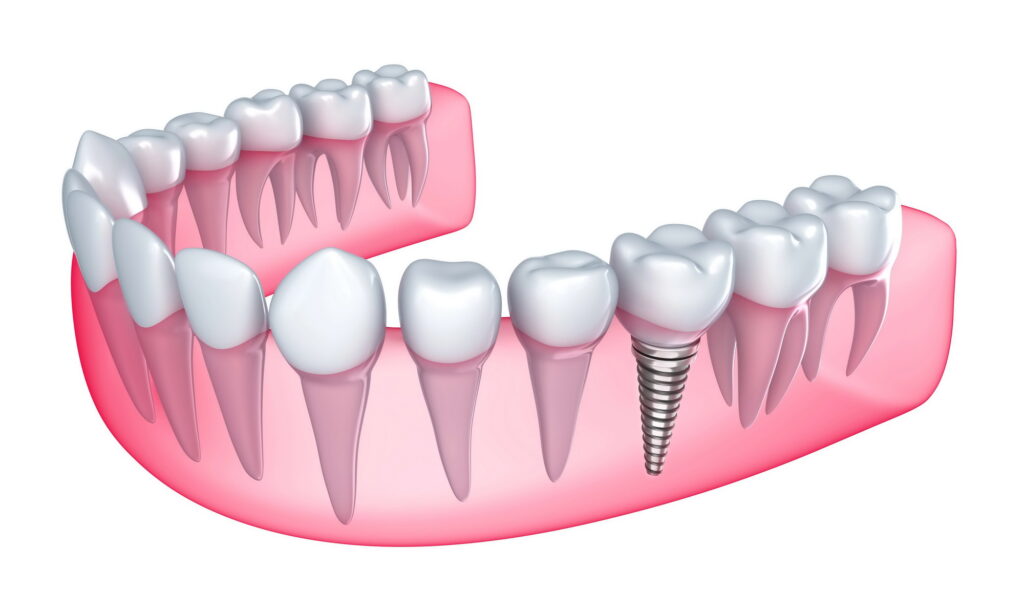

Τα Εμφυτεύματα Δοντιών αποτελούν υποκατάστατα των οδοντικών ριζών που έχουν χαθεί ή πρόκειται να εξαχθούν. Στην ουσία, είναι βίδες κατασκευασμένες από τιτάνιο, ένα υλικό που είναι απόλυτα βιοσυμβατό με τον ανθρώπινο οργανισμό και χρησιμοποιείται με επιτυχία στην ιατρική για δεκαετίες. Ένα εμφύτευμα αποτελείται από τρία κύρια μέρη:

Βίδα

To εμφύτευμα, το οποίο τοποθετείται μέσα στο οστό της γνάθου, αντικαθιστώντας τη ρίζα του δοντιού.

Κολόβωμα

Ή αλλιώς abutment, που συνδέεται με τη βίδα και βρίσκεται στο ύψος των ούλων, λειτουργώντας ως βάση στήριξης.

Προσθετική εργασία

Στεφάνη ή γέφυρα που σταθεροποιείται στο κολόβωμα, αντικαθιστώντας το ορατό τμήμα του δοντιού.

Η λειτουργία τους βασίζεται στην οστεο-ενσωμάτωση, μια φυσική ικανότητα του οργανισμού όπου το οστό ενσωματώνει το τιτάνιο, δημιουργώντας μια σταθερή και μόνιμη βάση για το νέο δόντι.